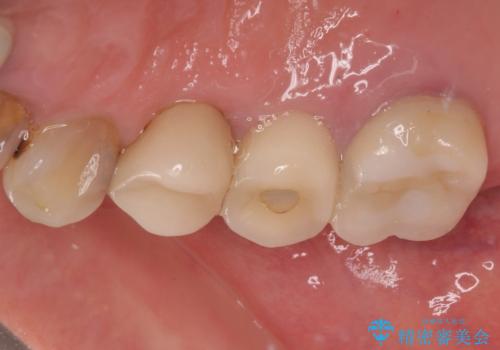

埋入時に十分な安定値が獲得でき、埋入した際に仮歯を装着することができました。

術後の経過は安定しており、抜歯から3ヶ月で治療を終えることができました。